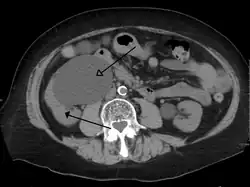

CT scan of bilateral hydronephrosis due to a bladder cancer -

Massive hydronephrosis as marked by the arrow -